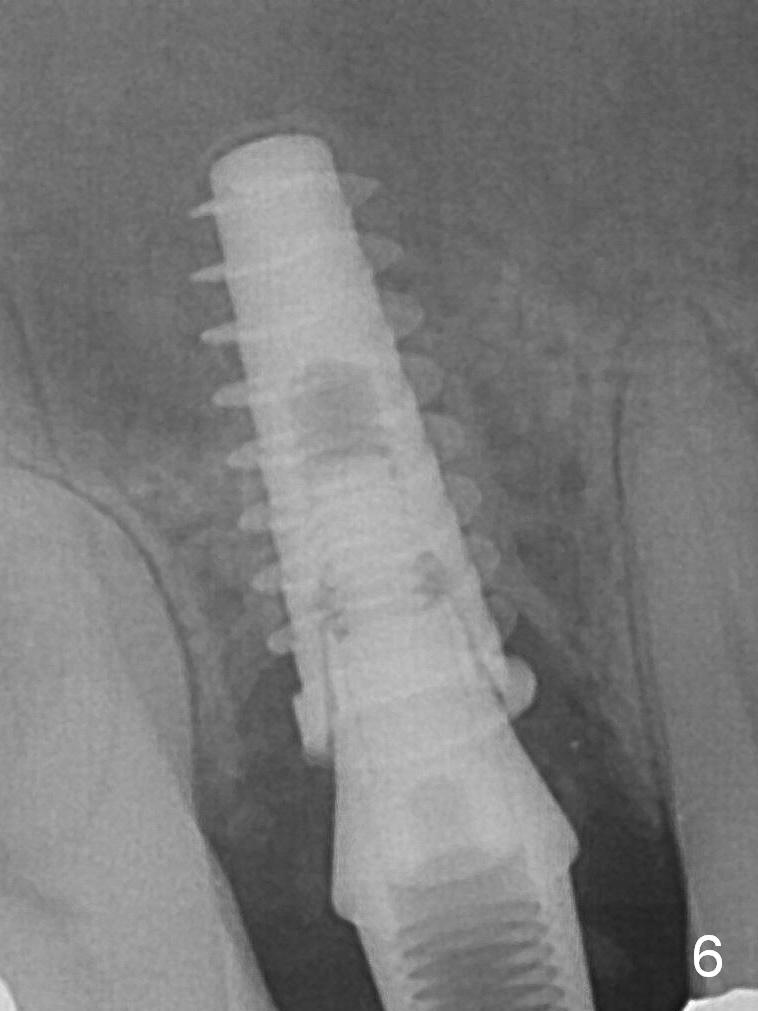

To prevent sinus lift related sinusitis, a shorter implant is going to be placed (Fig.1), approximately 2 mm beyond the apex.  Following extraction, the buccal plate (Fig.3a (coronal section): B) is not only ~ 2 mm shorter than the palatal one (P), but also thinner.  Since the bone density of the palatal plate is higher, without osteotomy an implant is less likely placed in the middle of the socket (S (Fig.1); Fig.3b) than buccal (Fig.3c).  Therefore drills are used to form osteotomy in the apical 1/3 of the palatal slope (Fig.3d (red arrow); SM: sinus membrane).  When 3.3 mm Magic Drill (MD) is in place (Fig.2), the distal surface of the sinus septum is perforated without air leakage.  Demineralized allograft (.0125-.085) is placed for sinus lift (Fig.4 *) prior to placement of 4.5x11 mm implant with ~ 30 Ncm.  The implant is slightly buccal to the ideal position indicated in Fig.3e (curved blue line: sinus lift).  A 4.5x4(2) mm pair abutment is placed for an immediate provisional to hold mineralized allograft in the remaining socket gaps (Fig.4 arrowheads, .5-1.5 mm).  A 9 mm implant may avoid sinus floor perforation on the distal slope of the 2nd premolar.  The osteotomy should have been established initially as mesial as possible.  In fact the patient has nasal hemorrhage while sneezing for the first 2 days postop.  Although he complains of pain buccal to the implant, the gingiva appears to heal 7 days postop (Fig.5).  The distobuccal papilla appears to be displaced somewhat.  Raising mucoperiosteal flap is most likely associated with postop pain and esthetic compromise.  The implant appears to have osteointegrated 5 months postop (Fig.6).  A 4.5 mmx15° 3 mm cuff angled abutment is placed for final restoration.  The distolingual portion of the implant is supported by the regenerated bone 3 years post cementation (Fig.7,8).  There is no bone loss 4 years 2 months post cementation (Fig.9,10).